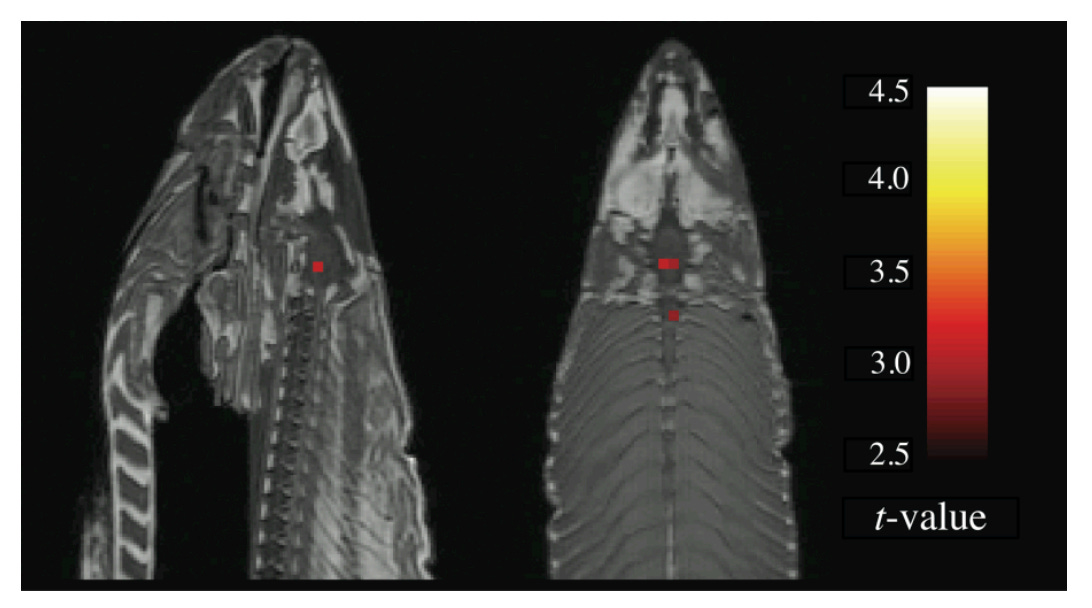

While there’s potential in fMRI, we’re still reasonably far from finding it. If it were to appear on the hype cycle, it would probably be on the downward slope after the peak of inflated expectations. Unfortunately, studies are often tiny because of the high costs of running the machine and interpreting the results and the data can be tough to interpret. A 2009 study of a salmon, for instance, showed the “fish’s brain exhibited increased activity for emotional images.” The only problem? The fish was dead. “Even in a dead salmon’s brain,” explains Kelsey Ichikawa in a new Nautilus piece, “the MRI scanner detected enough noise that some voxels exhibited statistically significant correlations. By failing to correct for multiple comparisons, Bennett and his colleagues ‘discovered’ illusory brain activity.”

For a sense of scale, the brain contains an estimated 100 billion neurons, and a single voxel in the human cortex can cover over 500,000 neurons. Those neurons may be doing any number of things—exciting each other, inhibiting each other, or firing in different patterns within sub-populations—but all that fMRI can detect is the net change in oxygenated blood over that whole voxel space every 2 seconds. This is like trying to determine the average opinion on foreign policy from 500,000 different people arguing, agreeing, and debating simultaneously.

To some extent, the concept of certain regions “lighting up” is a function of the images the machines spit out. “The eye-catching blobs and connectivity maps exist because of the particular way in which neuroscientists, magnetic resonance physicists, and data scientists decided to visualize and represent data from the brain,” Ichikawa concludes. The perfect picture, in other words, continues to elude us. (NRB)